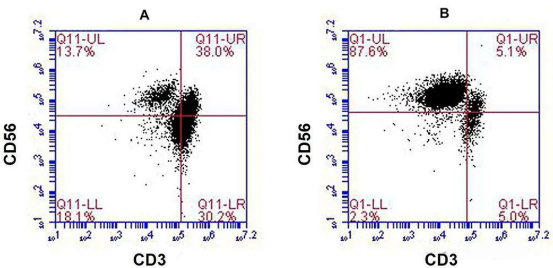

令患者本人和医疗团队都格外惊喜的是,7个月后,患者的胸水和腹水明显减少,治疗17个月后,CT扫描显示他肝右叶的多个肿瘤显著缩小。淋巴细胞亚群出现的变化表明免疫功能得到改善。此外,患者的肝功能水平和白细胞、血小板、中性粒细胞和淋巴细胞计数也保持在参考范围内。

NK细胞被定义为“CD3-CD16+CD56+”的淋巴细胞,是人体第三类淋巴细胞,又被誉为天然免疫的核心细胞,如果将我们的免疫系统比作身体防御的精锐部队,那么自然杀伤细胞(NK细胞)就是其中反应最迅速的特种兵。它们约占人体外周血淋巴细胞的5%-15%,是先天免疫系统的核心力量。

上文提到的晚期肝癌患者程先生,正是通过15个月的NK细胞输注,使体内NK细胞比例提升近7倍,同时CD8+T细胞等关键免疫指标显著改善。影像学检查显示其胸腹水消退,肝部肿瘤缩小,生存期远超预期。